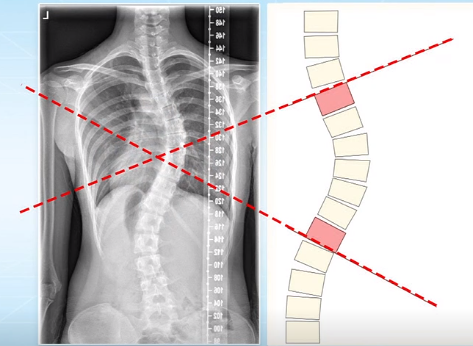

脊柱側(cè)彎的角度測量